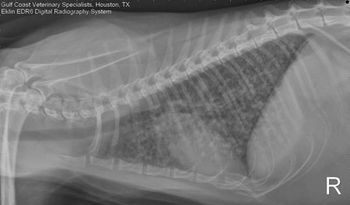

Correct answer Image Quiz: A panting Great Dane with red eyes